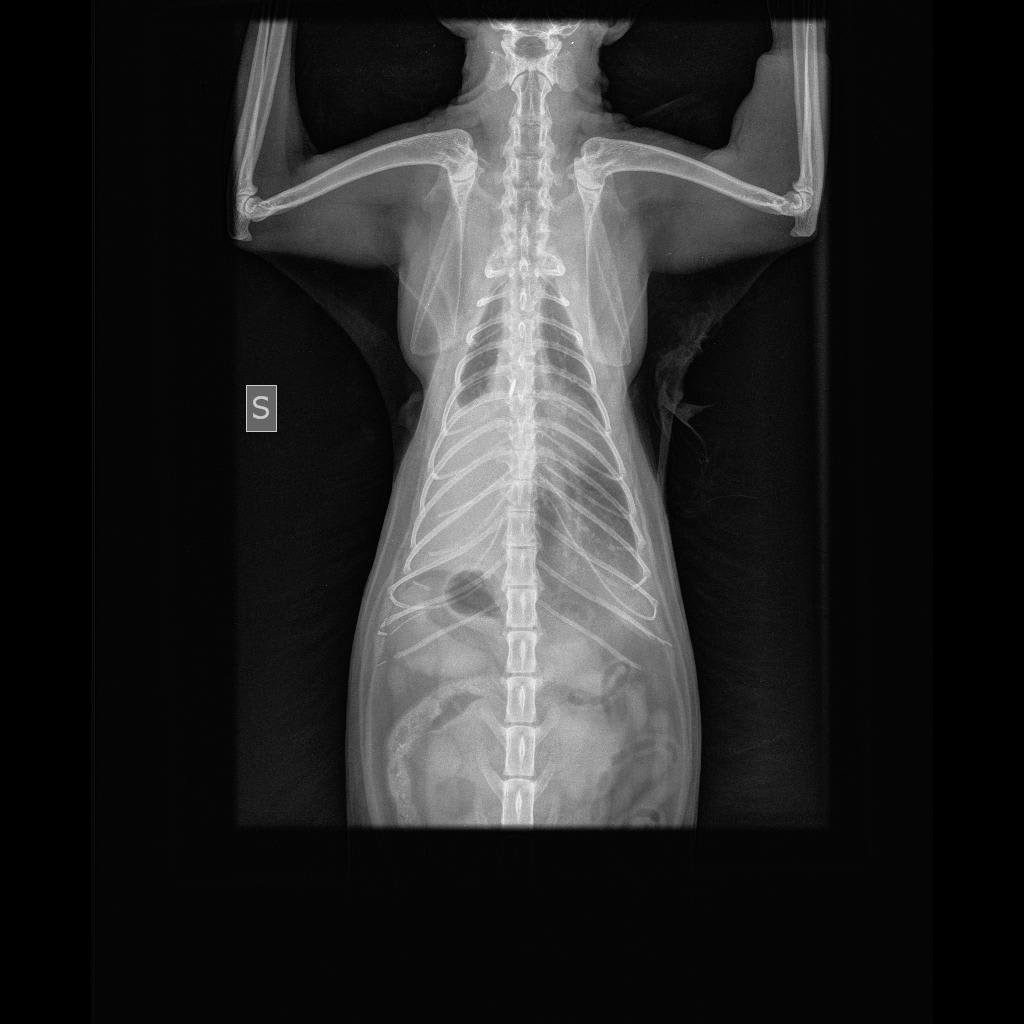

Pet's info: Cat | Domestic Longhair | Female | spayed | 8 years and 7 months old | 8 lbs

Hello, my 8 year old cat was just recently diagnosed with diaphragmatic hernia (unsure when she got it) which is making her eating efforts a bit difficult. She's lost some weight over the past month and will only eat a good meal if I am there to help her. My vet suggested she has surgery as soon as possible, but my mother has knowledge of cats living with the condition just fine and argued my vet may be after money. Since I know this surgery is extremely delicate... Can I get an advice on this?